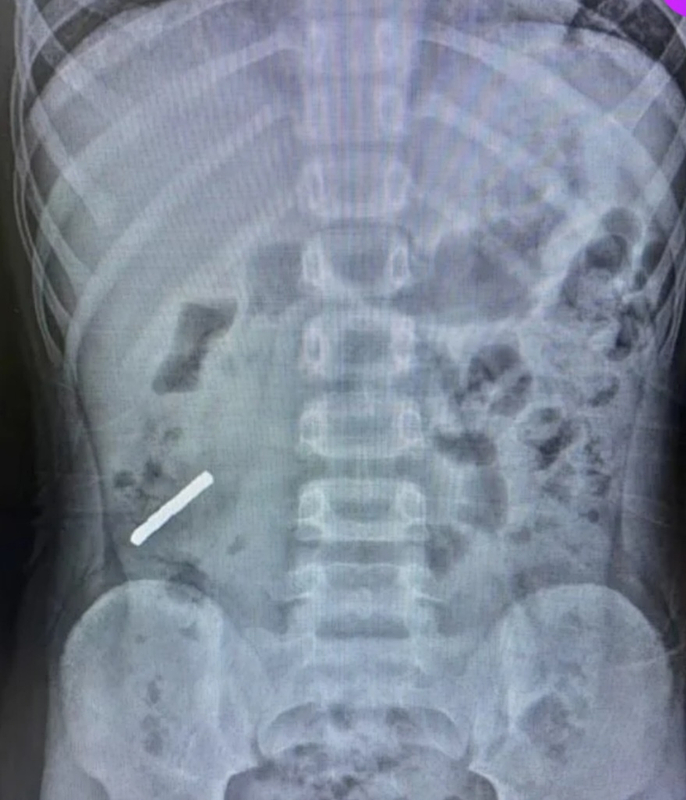

4岁童腹痛求诊 X光揭吞磁力玩具